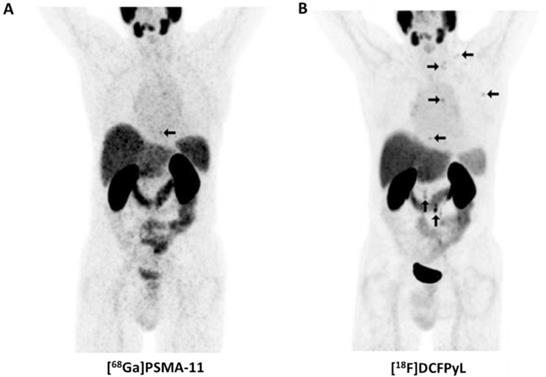

Figure 6

Head-to-head comparison of [68Ga]PSMA-11 vs. [18F]JK-PSMA-7. Whole-body distribution of [68Ga]PSMA-11 (A) vs. [18F]JK-PSMA-7 (B) in the same patient. [68Ga]PSMA-11 revealed only one PSMA-positive retroperitoneal paraaortal lymph node (blue arrow), whereas the [18F]JK-PSMA-7 PET/CT showed two PSMA-positive retroperitoneal lymph nodes (blue arrows). Modified from Dietlein et al. [109], © by the Society of Nuclear Medicine and Molecular Imaging, Inc.

Clinical Investigations. In vivo data has been acquired in a first-in-human study as well as in a biodistribution and dosimetry study (n=10) [80], in a direct comparison with [68Ga]PSMA-11 (n=10) and in clinical applications in a larger clinical population (n=124, Figure 6) [81]. These studies demonstrate physiologic radiotracer accumulation in a pattern resembling the distribution known from other PSMA-targeted radiotracers with excretion via urinary and biliary pathways. Regarding dosimetry, whole body doses similar to other radiotracers were reported, with a maximum in the kidneys. High uptake in suspicious lesions was found, increasing over time, suggesting benefits of a late start of the PET/CT acquisition [80]. A pilot study in 10 patients who were examined with both PSMA-targeted radiotracers demonstrated that [18F]JK-PSMA-7 was at least equivalent to [68Ga]PSMA-11, as all [68Ga]PSMA-11-positive lesions could be seen with [18F]JK-PSMA-7 and several additional lesions were detected. In a subsequent analysis of a larger clinical cohort, [18F]JK-PSMA-7 was found useful in various diagnostic scenarios (initial staging, biochemical recurrence and therapy monitoring). Notably, in patients with biochemical recurrence after prostatectomy (PSA level, ≥ 0.17 ng/ml) or in patients with biochemical recurrence after radiation therapy (PSA levels, ≥ 2 ng/ml), PSMA-positive lesions were detected in 44/53 patients (83%) [81]. Direct comparison with other 18F-labeled PSMA-targeted radiotracers appears warranted, in particular as sensitivity for [18F]DCFPyL has been described moderately lower in a similar clinical scenario (74.2%) [81].